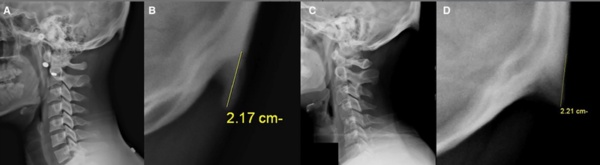

2. Avustralya’daki Sunshine Coast Üniversitesi’den bilim adamları Dr. David Shahar ve Prof. Mark Sayers, 18-30 yaş arasındaki 218 kişinin röntgen çekimlerini inceledi. Yapılan araştırmalar sonucu röntgen çekilen kişilerin neredeyse yarısının kafatası şeklinin yoğun cep telefonu ve tablet kullanımına bağlı olarak ‘değiştiği’, boynuzumsu bir çıkıntıya benzediği belirtildi.

Avustralya’daki Sunshine Coast Üniversitesi’den bilim adamları Dr. David Shahar ve Prof. Mark Sayers, 18-30 yaş arasındaki 218 kişinin röntgen çekimlerini inceledi. Yapılan araştırmalar sonucu röntgen çekilen kişilerin neredeyse yarısının kafatası şeklinin yoğun cep telefonu ve tablet kullanımına bağlı olarak ‘değiştiği’, boynuzumsu bir çıkıntıya benzediği belirtildi.

6. Ensenin üstünde sivrilen 10-30 milimetre arasında değişen çıkıntıya, &#8216;dış oksipital kabartı&#8217; deniyor. Dış oksipital kabartıya, taşınabilir dijital cihazlar yaygınlaşmaya başlamadan önce daha çok yaşlı insanlarda rastlandığı, gençlerde ise oldukça nadiren rastlandığı belirtiliyor.

Ensenin üstünde sivrilen 10-30 milimetre arasında değişen çıkıntıya, ‘dış oksipital kabartı’ deniyor. Dış oksipital kabartıya, taşınabilir dijital cihazlar yaygınlaşmaya başlamadan önce daha çok yaşlı insanlarda rastlandığı, gençlerde ise oldukça nadiren rastlandığı belirtiliyor.